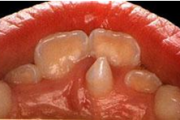

Emaili hüpoplaasiad

muutused hammaste kujus

Amelogenesis Imperfecta

Hamba atritsioon